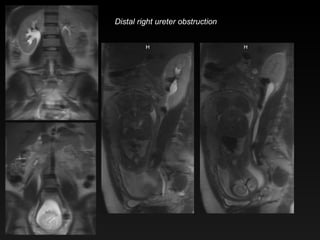

Distal right ureter obstruction

Hydronephrosis & PregnancyHydro of pregnancy Usually mild Right > Left ureter tapers between uterus and psoas No perinephric edema Ureteral obstruction Perinephric edema Ureter cutoff below or above uterus May see filling defect Don’t be fooled by flow artifact on HASTE/SSFSE

Hydronephrosis & Pregnancy Hydro of pregnancy Usually mild Right > Left ureter tapers between uterus and psoas No perinephric edema Ureteral obstruction Perinephric edema Ureter cutoff below or above uterus May see filling defect Don’t be fooled by flow artifact on HASTE/SSFSE